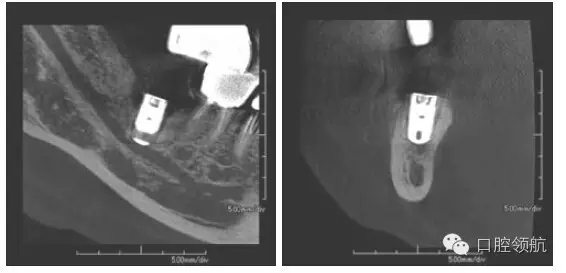

術(shù)后第2天,右側(cè)頦神經(jīng)區(qū)域感覺異常來本院診療,曲面斷層和CBCT影像顯示,種植體的尖端接觸到了下頜神經(jīng)管(圖1、圖2)。

圖2 植入后的CBCT影像。